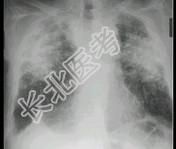

- 单项选择题男,52岁, 从事矿井工作32年,近几年出现气喘, 呼吸困难,X光片如图, 其最可能的诊断为 ( )

A、双肺浸润性结核

B、双肺真菌感染

C、两肺弥漫性间质性肺炎

D、两肺弥漫性纤维化

E、硅沉着病病